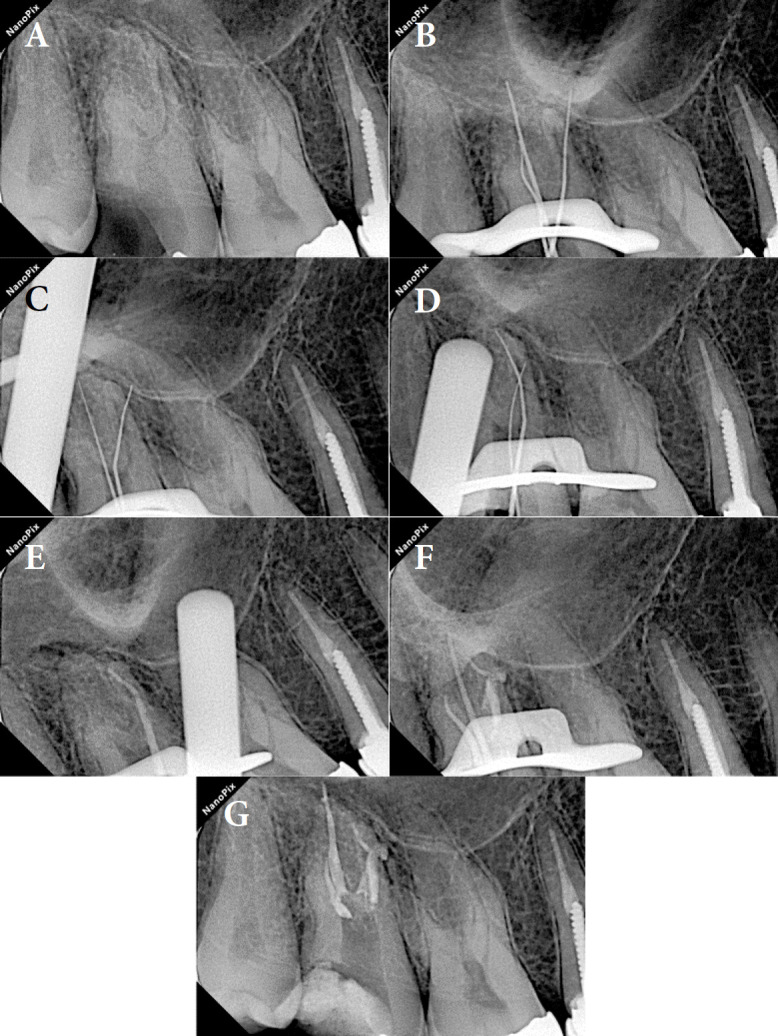

Taurodontism is a dental anomaly characterized by an enlarged pulp chamber and apically displaced pulpal floor. This disorder poses significant challenges in endodontic treatment, especially when perforations occur. The present case study details the endodontic retreatment of a hypertaurodont maxillary second molar in a 36-year-old female patient with a mesial canal perforation. The procedure employed a dental operating microscope for enhanced visualization and precision. Canals were prepared using a crown-down technique, with the perforation site managed using MTA and bioceramic material applied via the second mesiobuccal canal. The remaining canals were obturated using gutta-percha and bioceramic sealer. At the 1-year follow-up, the tooth was functional and asymptomatic, with radiographic evidence of a normal periodontal ligament space. This case demonstrates the efficacy of contemporary endodontic techniques, including bioceramic materials and advanced magnification, in managing the unique challenges posed by taurodontism.